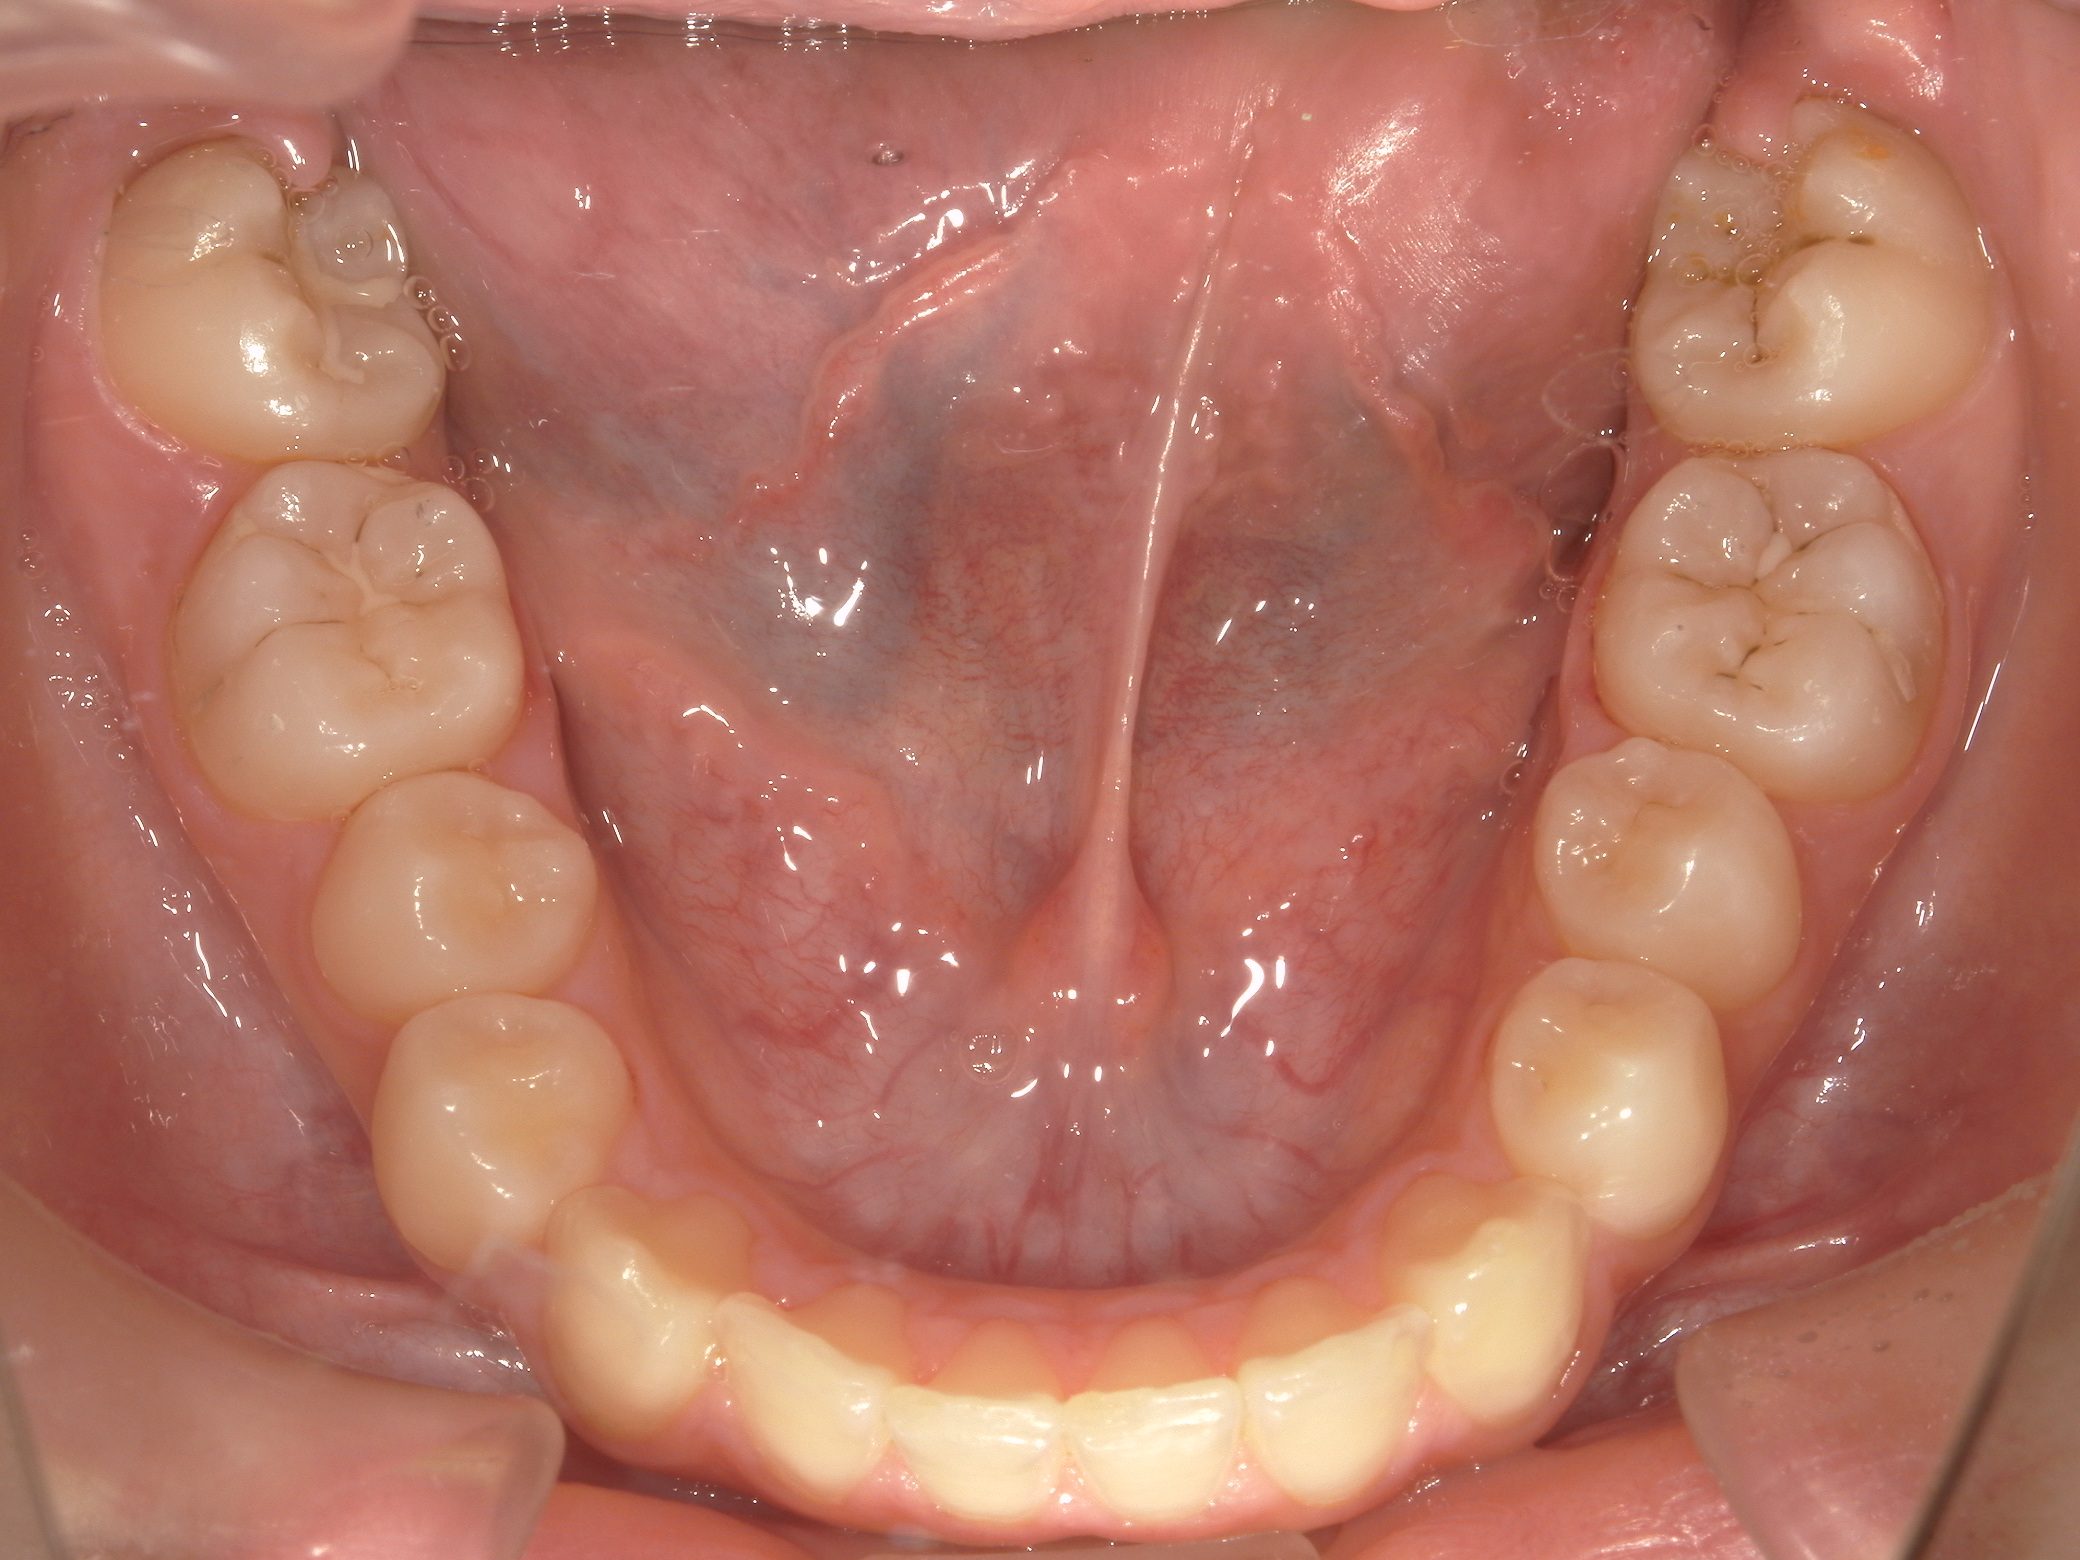

【小学生】 8歳 マイオブレース矯正 + インビザライン矯正 叢生(でこぼこ)を改善

Before

After

治療期間

3年年

治療開始

8歳

種類

マイオブレース矯正 + インビザライン矯正

使用装置

マイオブレース 3Dリンガルアーチ インビザライン

コメント

1期治療後 叢生(でこぼこ)が少し残ったので インビザラインで治しています

現在も 維持してくれています